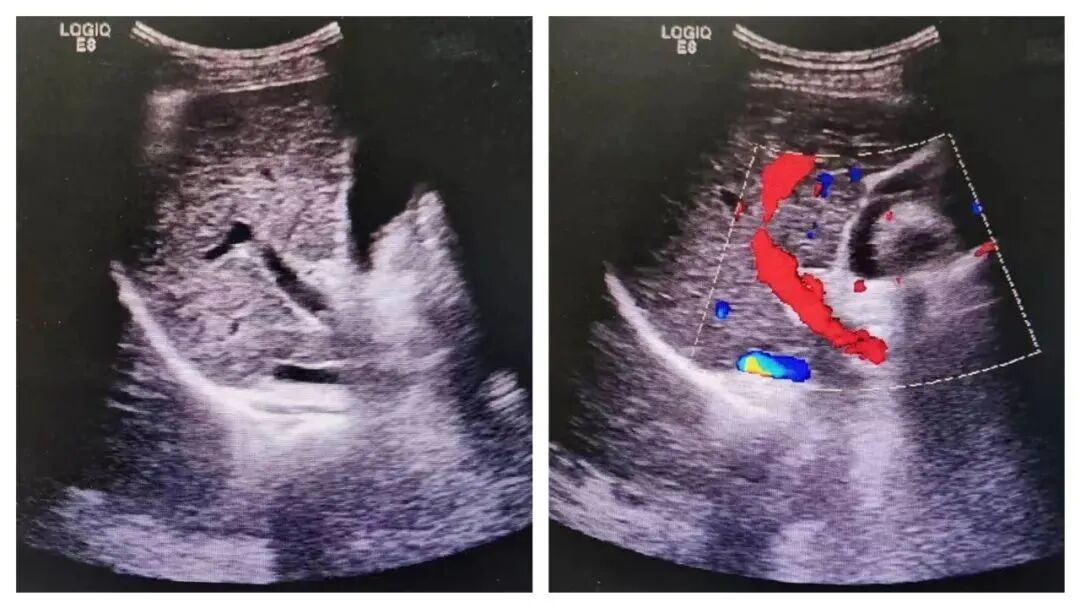

因此,在做彩超检查时,显示器上显示的多数是黑白的二维图像,在需要观察脏器血流情况、加上彩色多普勒时,才会在黑白图像上叠加彩色血流图像。

多普勒彩超图怎么看【妇幼科普】涨知识,明明做了“彩超”,为什么图像是黑白的?_https://www.jmylbn.com_新闻资讯_第5张  这样大家就明白了,彩超大部分图像仍是黑白图像,只有在检查血流信息时才呈彩色图像。

左图为黑白B超显示肝脏的结构,右图加上彩色多普勒功能清晰显示肝脏血管分布